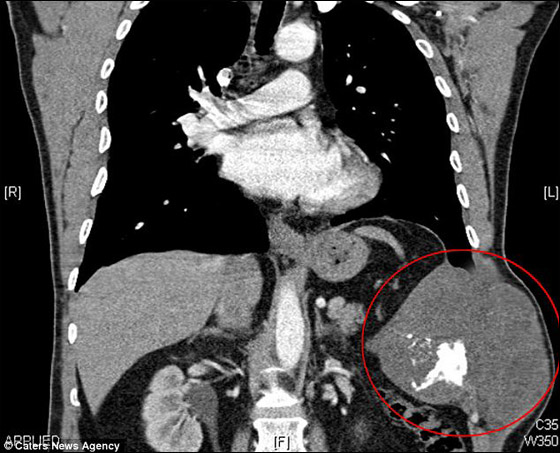

أعاد فريق طبي ترميم صدر مريض بريطاني باستخدام غلاف من الخرسانة بعد استئصال ورم في حجم البطيخة من بين أضلاعه. واكتشف الأطباء أن ماريك باردين (40 عاما) العامل في كنيسة مصاب بالسرطان في أغسطس/اب 2011 بعد أن اشتكى من وجود تورم في منطقة الصدر. وخضع خلال خمسة أسابيع من اكتشاف الورم إلى 6 عمليات جراحية لإزالة الورم وبطانة الرئة اليسرى، وستة أضلاع وجزء من الحجاب الحاجز.

ولحماية صدره بعد نزع بعض أضلاعه تم تغليفه بقالب بلاستيكي مملوء بالخرسانة حجمه 25 سم وسمكه 4 ملليمتر، وتم استخدام جزء من عضلات الكتف في إصلاح مشكلة الحجاب الحاجز، بحسب صحيفة "ديلي ميل" البريطانية.